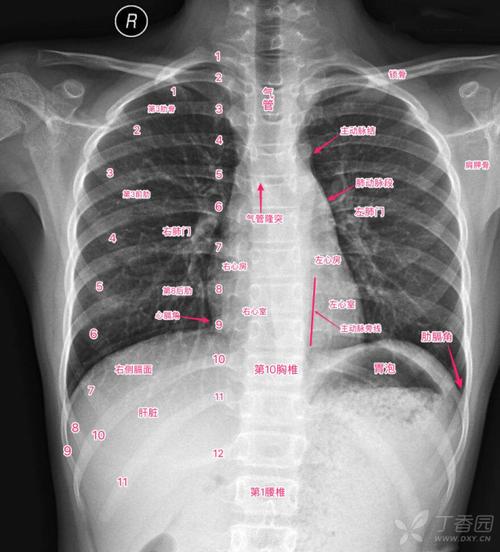

超详细胸片教学 不信你还学不会!

"0"基础小白必备宝典:认识肺部影像结构

正常胸片图片图解

肺部正常胸片影像图片

正常胸片影像图片